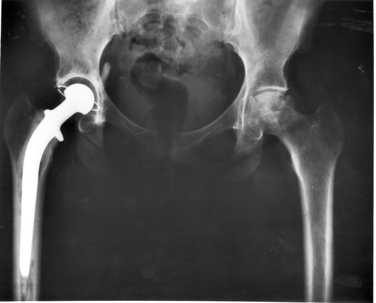

Osteolysis is the breakdown and resorption of bone tissue. Artificial joint replacements, like metal hip replacements, can trigger osteolysis.

Metal hip osteolysis: the replacement metal hip can cause the metal joints to be worn down. Activity and excessive use wears away metal particles from the prosthetic. These particles trigger the immune system to fight as your body thinks this is potentially harmful to your health. This can result in healthy bone tissues being reabsorbed (osteolysis). The resorption of healthy tissues causes your bones to weaken and increases the chance of breakages and bone fractures.

Osteolysis has been seen in some patients 12 months after receiving a metal hip implant. If you have osteolysis, it’s likely you will need future surgery to replace the metal hip to stop further bone damage.